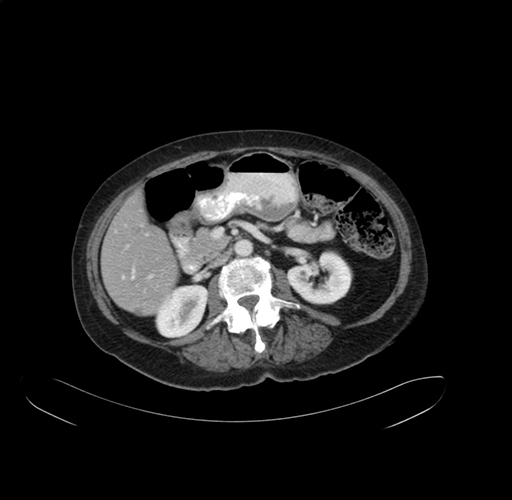

Axial Venous